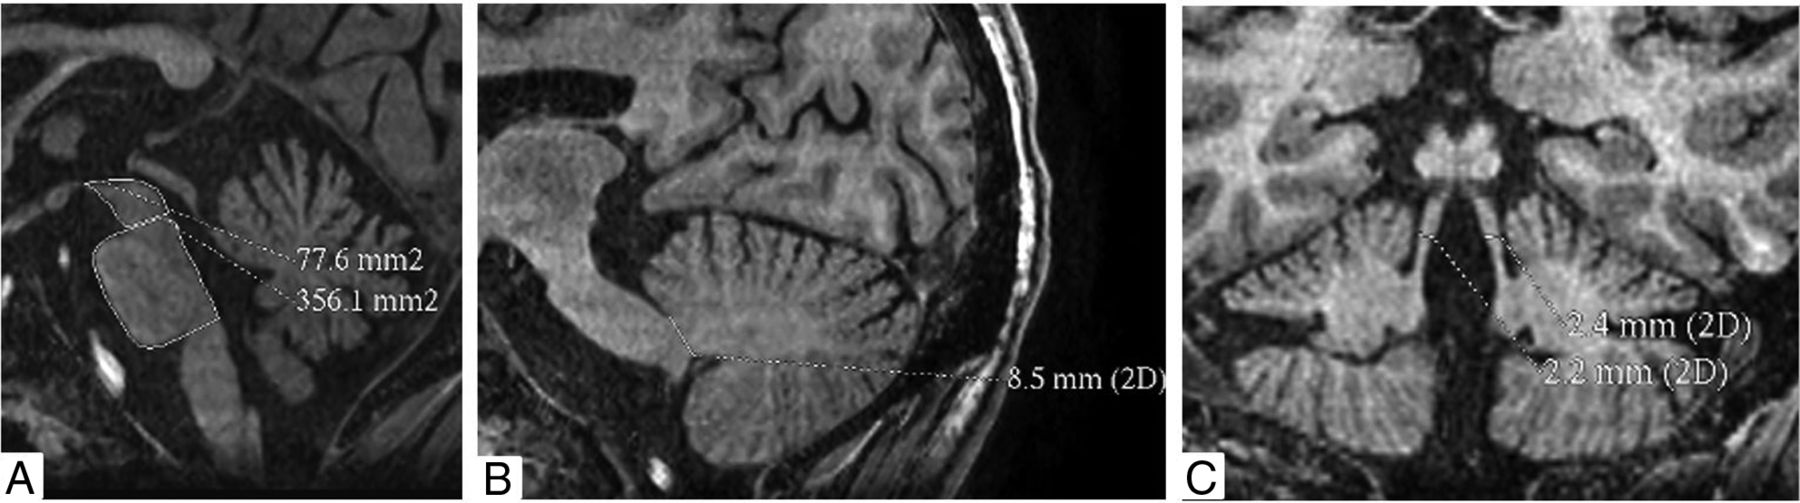

The midbrain and pons areas were measured on the midsagittal 3D BRAVO sequence. A line passing through the superior pontine notch and the inferior edge of the quadrigeminal plate was taken as the demarcating line between midbrain and pons. A second line parallel to the first line passing through the inferior pontine notch was taken as the lower margin of the pons. The midbrain area was traced around the edges of the midbrain tegmentum above the first line. The tectum of the midbrain was not included. The pons area was included craniocaudally between the 2 above-mentioned lines and along the anterior and posterior margins of the pons anteroposteriorly. The width of the middle cerebellar peduncle (MCP) was measured on parasagittal views of the 3D BRAVO sequence. Left and right MCPs were identified on parasagittal views on which the MCP was best exposed between the pons and the cerebellum. The distance between the superior and inferior borders of the MCP was measured, as delineated by the peripeduncular CSF spaces of the pontocerebellar cisterns. Each MCP width (left and right) was measured, and a mean value for the 2 MCPs was calculated. The superior cerebellar peduncles (SCPs) were measured on the coronal views of the 3D BRAVO sequence. In the coronal view, images were inspected in the anteroposterior direction parallel to the axis of the brain stem to identify the SCP. The linear distance between the medial and lateral borders of the superior cerebellar peduncle was measured at the middle of their extension, and an average of the 2 SCPs was calculated. The ratios of pons-to-midbrain area and MCP-to-SCP width (MCP/SCP) were also used, and the MRPI was calculated by Pons Area / Midbrain Area × MCP width/SCP width (Fig 1).11

Cranial MR imaging in the BRAVO 3D sequence showing the protocol of measurement of the midbrain and pons areas (A), width of the middle cerebellar peduncle (B), and width of the superior cerebellar peduncle (C).

Cranial MR imaging of a 31-year-old woman with Wilson disease shows increased pons-to-midbrain areas (4.59 mm2) (A), reduced width of the middle cerebellar peduncle (8 mm) (B), and a reduced width of superior cerebellar peduncle (2.3 mm) (C). Her MR Parkinsonism index was increased (16.9). She had impaired postural reflex.